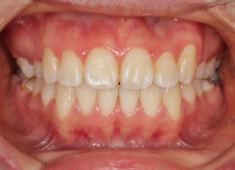

治療後(2年後)